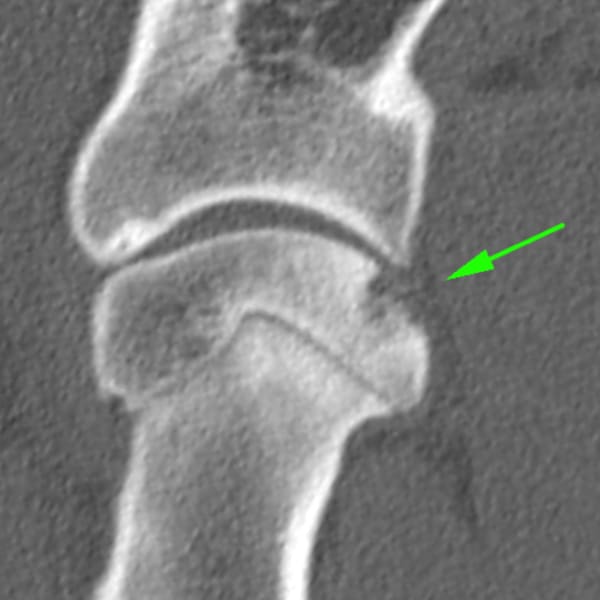

El diagnóstico de esta enfermedad se alcanza generalmente mediante la combinación de una completa exploración ortopédica y estudios de imagen como radiografías y / o tomografía computarizada.